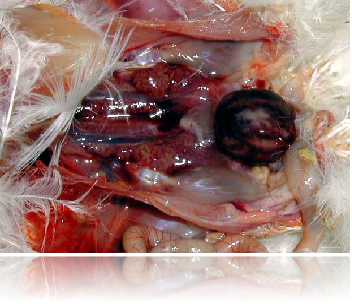

法氏囊出血